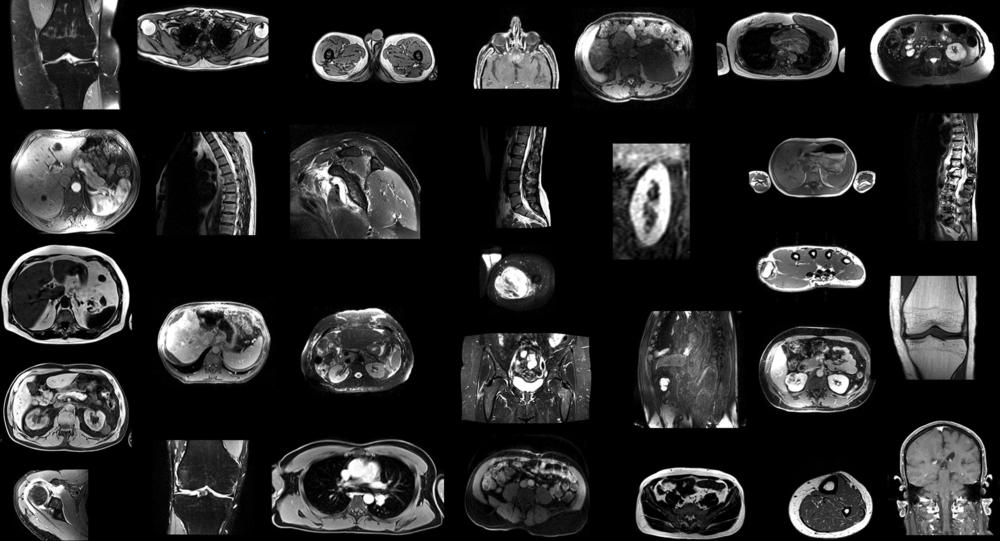

Figure 1. Example MRI scans in the training dataset. Since images were randomly sampled from clinical routine, the dataset (n = 561) contains a wide variety of different contrasts, pathologies, and image types.